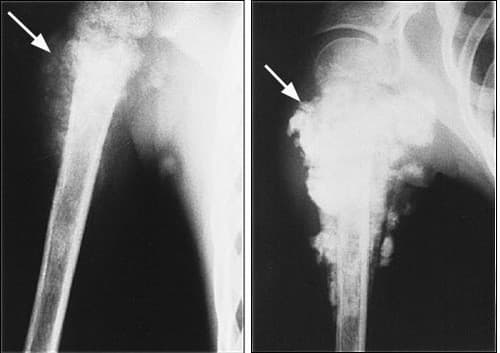

– Chụp X quang

CHẨN ĐOÁN BỆNH SARCOMA TẠO XƯƠNG

TRIỆU CHỨNG BỆNH SARCOMA TẠO XƯƠNG